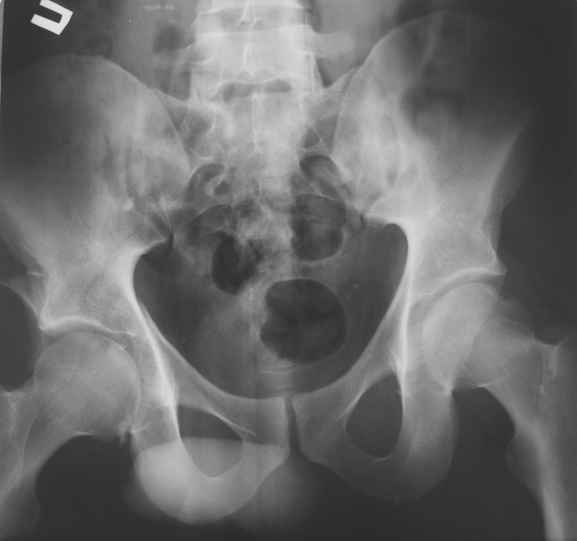

Пациент 30 лет поступил к нам в клинику по поводу закратого поперечного перелома свода, перелома задне -вехнего края правой вертлужной впадины, подвздошного вывиха правого бедра. Постравматического неврита правого седалищного нерва. Закрытого запирательного вывиха левого бедра. травма автодорожная 3 недели назад. Вправление вивихов при поступлении по месту жительства, получал скелетное вытяжение (слева в течении 2 недель).

На контрольной Р-грамме обнаружена импрессия верхнего полюса головки левого бедра. Выполнено КТ.

Подскажите пожалуйста, необходимо что либо предпринимать по поводу перелома головки левого бедра (в "Мюллере" описана костная пластика дефекта)? И как рано можно разрешить нагрузку на левую ногу.